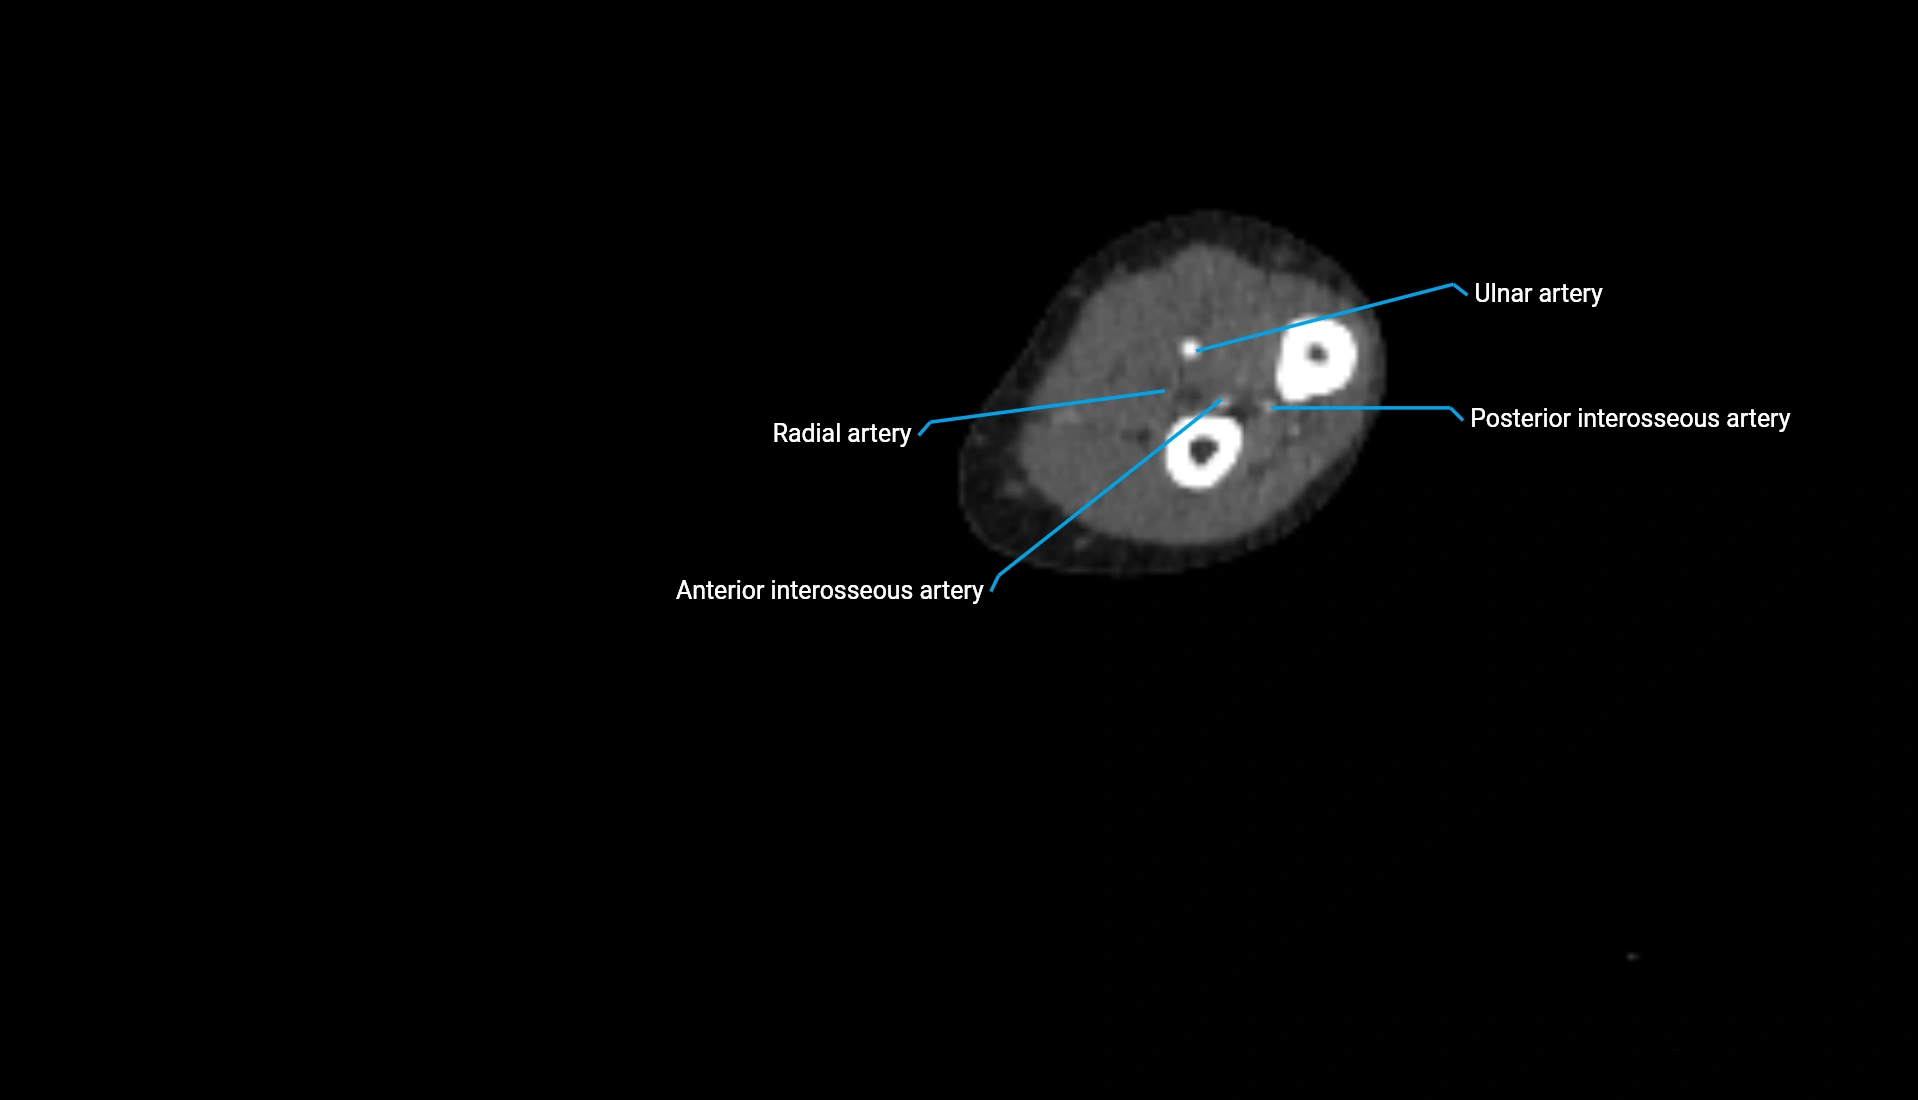

CT Appearance

Non-Contrast CT:

• Cortex: High-density, sharply defined

• Subchondral bone: Dense cancellous matrix

• Articular surface: Smooth concave contour articulating with the capitellum

• Excellent for evaluating bone integrity, alignment, and subtle fractures